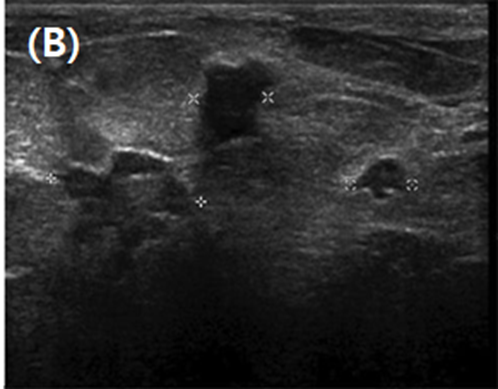

Figure 2. Targeted ultrasound demonstrates multiple small, irregular, and loculated solid hypoechoic lesions, correlating with mammographic findings.

Sonography typically reveals:

Multiple hypoechoic, irregular, or lobulated intraductal masses

Lesions are usually <1 cm in size

Vascular stalks are evident on color Doppler